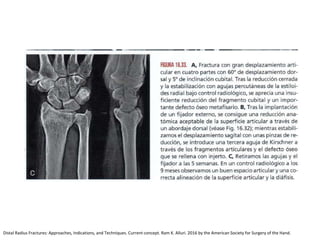

Reducción abierta + Fijación Interna

Distal Radius Fractures: Approaches, Indications, and Techniques. Current concept. Ram K. Alluri. 2016 by the American Society for Surgery of the Hand.